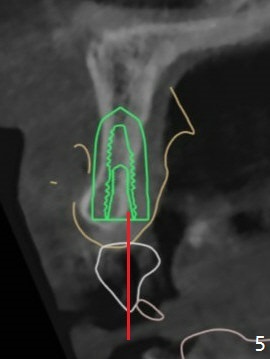

The patient has gummy smile (Fig.1).  The edentulous ridge at #10 has buccal concavity (Fig.2 *).  The surgical guide fits well without #9 distal trimming.  With 34 mg Xylocaine and 17 mcg Epinephrine infiltration at #10 and 12, the patient feels pain when 2.2 (in fact 1.9) x8.5 mm drill is being used.  When Septocaine is added, the osteotomy at #10 is found distal.  Out of curiosity, PA is taken with 2.2x10 mm drill in place; its trajectory seems satisfactory (Fig.3).  When a 2.5x13 mm 1-piece implant is placed free hand, it deviates palatal, which is confirmed with incision after addition of 34 mg Xylocaine and 34 mcg Epinephrine.  A new osteotomy is created by S-Mini Kit buccal to the previous one.  With Lindamann bur to adjust the position of the new osteotomy twice, the last drill (2.0 mm) apparently starts to perforate the apical portion of the buccal plate.  The perforation seems to enlarge when the mini implant is re-placed (Fig.4, 8 (green area) <30 Ncm).  With Vanilla graft (Fig.8 pink circles) and abutment height adjustment (Fig.4), a provisional is fabricated with occlusal clearance.  There are two reasons for failure of the surgical guide: failure to trim the tooth #9 distal (minor palatal guide displacement, Fig.5) and deflection of pointed drill and 2.2 mm drills over the hard palatal plate slope (Fig.6).  To avoid this complication, the pointed drill should be done free hand initially, after incision and obliquely (Fig.7).  The guide is placed to finish the rest of osteotomy if deem to be appropriate.